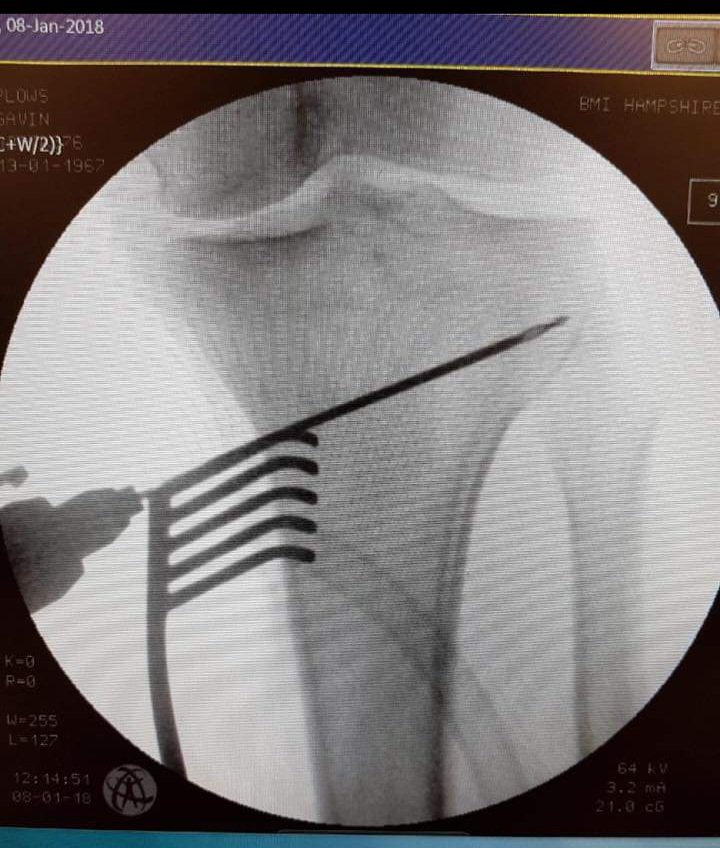

So I'm guessing, OF watercooler, a place to shoot the shit kinda thing😀, so questions, anybody got any metal in them?

I took a bit of a tumble 3 weeks ago while skiing, ended up with this, left tibia fractures.

Anybody got something similar, how did it work out? I'm all good, just need to be patient now, fortunately time I have so one day at a time.

Thanks, it's titanium, and my understanding is that it will stay in, until I need a new knee, 10 to 15 years. Fortunately no real pain, just uncomfortable, I'm lucky.

Had something similar about 6 years ago. Worked out OK. Some nerve damage so loss of feeling down front of leg and some reduction in flexibility but all in all a success story.

Follow all the guidelines and do exactly as advised